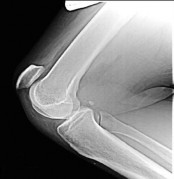

Question 19:

A 15-year-old male presents with chronic knee pain. MRI reveals a stable Osteochondritis Dissecans (OCD) lesion of the knee. Which of the following anatomic locations is the classic and most common site for an OCD lesion in the knee?

Options:

- Lateral aspect of the medial femoral condyle

- Medial aspect of the medial femoral condyle

- Central weight-bearing surface of the lateral femoral condyle

- Posterior aspect of the lateral tibial plateau

- Inferior pole of the patella

Correct Answer: Lateral aspect of the medial femoral condyle

Explanation:

The classic and most common location for an osteochondritis dissecans (OCD) lesion in the knee is the lateral aspect of the medial femoral condyle (often remembered by the mnemonic 'LAME': Lateral Aspect Medial Epicondyle/Condyle). It accounts for approximately 70-80% of knee OCD lesions.